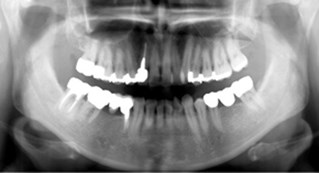

Helkäksröntgen (OPG)

I våra lokaler på Kungsgatan, finns det ett litet rum, "Silvia-rummet", som hyser vår digitala panoramaröntgen: OPG. Med denna röntgenapparat kan vi ta en bild av hela käken på en gång!

Du som patient står upp när bilden tas och du har ingen bildsensor inne i munnen, utan allt sker runt om käkens och huvudets utsida. Tidigare har vi varit tvungna att remittera våra patienter till en röngenspecialist för att få dessa bilder tagna. Panoramaröntgen behövs bl a inför implantatbehandlingar, vid käkskador, för bedömning av käkleder, men också vid förhandsprövningar till Försäkringskassan .

För att öka patientsäkerheten (att kunna hitta dolda tandinfektioner etc) kommer en sådan bild att tas på alla nya patienter vid första undersökningstillfället som en referensbild. Vi vill dessutom ta sådana bilder på samtliga patienter över 40 år som erhållit större fyllningar, genomgått rotbehandlingar - allt som ett led i att, på ett tidigt stadium, kunna upptäcka sjukdomsförändringar i både tänder, käkben och i angränsande vävnader.

Denna typ av röntgenundersökning ersätter inte de årliga s k "bitewings" vi tar för att kunna granska benhöjd och leta efter kariesangrepp med.